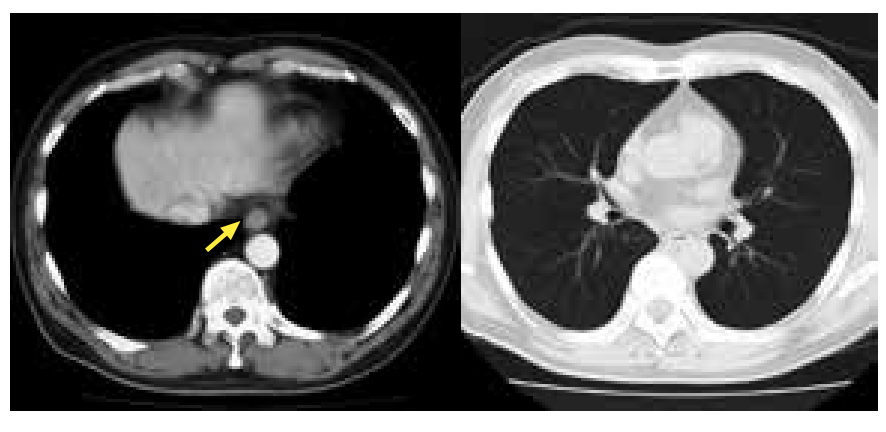

通过增强CT,可以看到肿瘤没有发生明显的转移,只局限于胸部下段食管。由于患者本人强烈希望进行内镜治疗,实施了ESD。

上图:通过HE染色,可以看到在组织间质中核质比(N/C)较高的细胞集聚。

下图:通过免疫组化染色,突触素(synaptophysin)和嗜铬粒蛋白A(chromogranin A)染色为阳性,疑为神经内分泌癌。